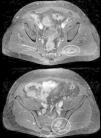

Presentamos el caso de un varón de 56 años que consultó en urgencias por fiebre y dolor en el glúteo izquierdo irradiado a la cara posterior del muslo, de 48 h de evolución. Tres días antes del inicio de los síntomas el paciente se había administrado una dosis de alprostadilo intrauretral como tratamiento de la disfunción eréctil secundaria a la prostatectomía por adenocarcinoma de próstata. En la exploración física destacaba dolor a la presión en la articulación sacroilíaca izquierda. Las maniobras de Lasêgue y de compresión del músculo piriforme del lado izquierdo fueron positivas. En la analítica destacaba una proteína C reactiva de 251mg/l (0-5) y procalcitonina 1,18ng/ml (< 0,25), sin leucocitosis ni desviación izquierda. La tomografía computarizada abdominopélvica (fig. 1) detectó la presencia de erosiones corticales predominantes en la vertiente ilíaca de la articulación sacroilíaca izquierda, en su mitad inferior, asociado a esclerosis subcondral, todo ello compatible con el diagnóstico radiológico de sacroilitis izquierda.